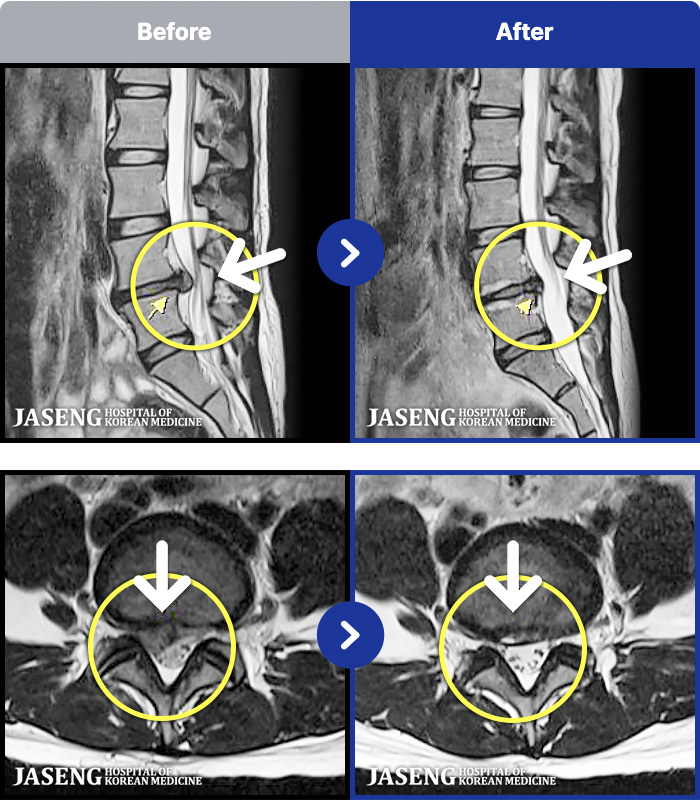

MRI ġ

1,240 MRI ũ ʸ Ȯϼ.